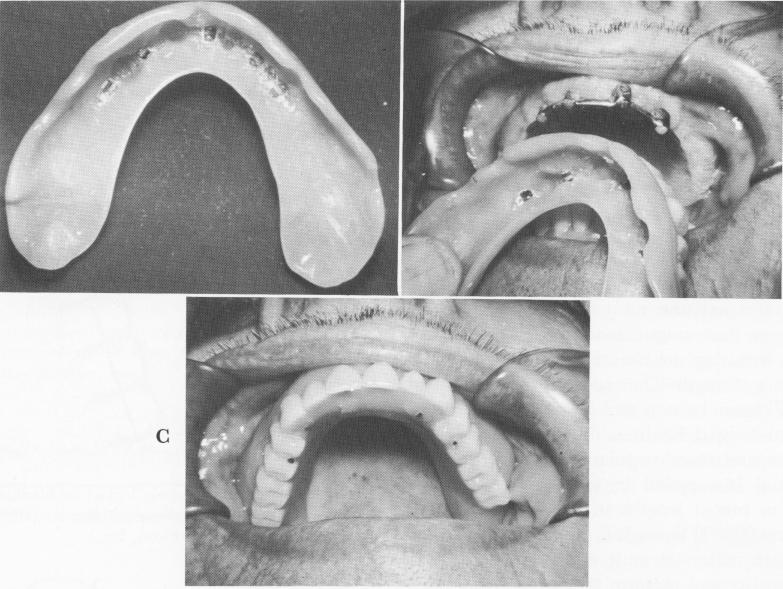

Fig. 7-73. An internal clip bar arrangement. A, The palateless denture with semicircular clip attachments, which is fitted over the dolder bar supporting the screw type implant (B). C, The arrangement permits a suitable palateless denture.

Resilient Gerber attachments are also often used as stress-breakers (Fig. 7-71). These may be combined with any type of abutment instead of only distal extensions. These Gerber attachments are used for tissue-supported cases and are often used with the dolder bar (Fig. 7-72). Another useful attachment is the internal clip bar (Fig. 7-73).

1 Palateless upper implant denture with semicircular attachments